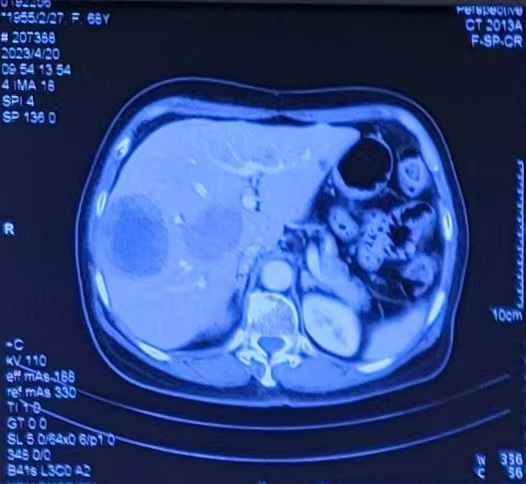

Progress of intrahepatic lesions shown on the abdominal CT after admission to our hospital.